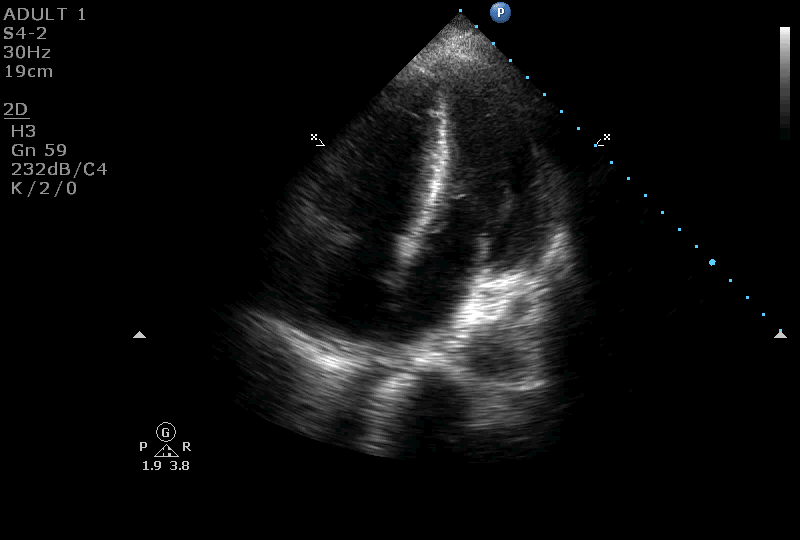

On further evaluation, the patient’s echocardiogram showed a 4.5 x 4.3 cm cystic tumor in the right atrium, hypertrophied obstructive cardiomyopathy with moderate left ventricular outflow tract obstruction, and good left ventricular function. She also underwent computed tomography (CT) and magnetic resonance imaging (MRI) of the chest, which revealed a neoplastic mass lesion, most likely right atrial myxoma.